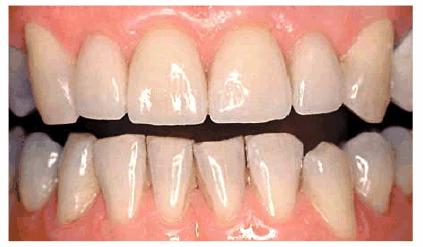

RESULT: The resulting smile with straighter and lighter teeth (Figures 24-7H, and 24-7I) was most appreciated by the patient.

Figure 24-7H: Pretreatment smile.

Figure 24-7I: Post-treatment smile with six maxillary full porcelain crowns and four mandibular incisors with bonded composite resins.